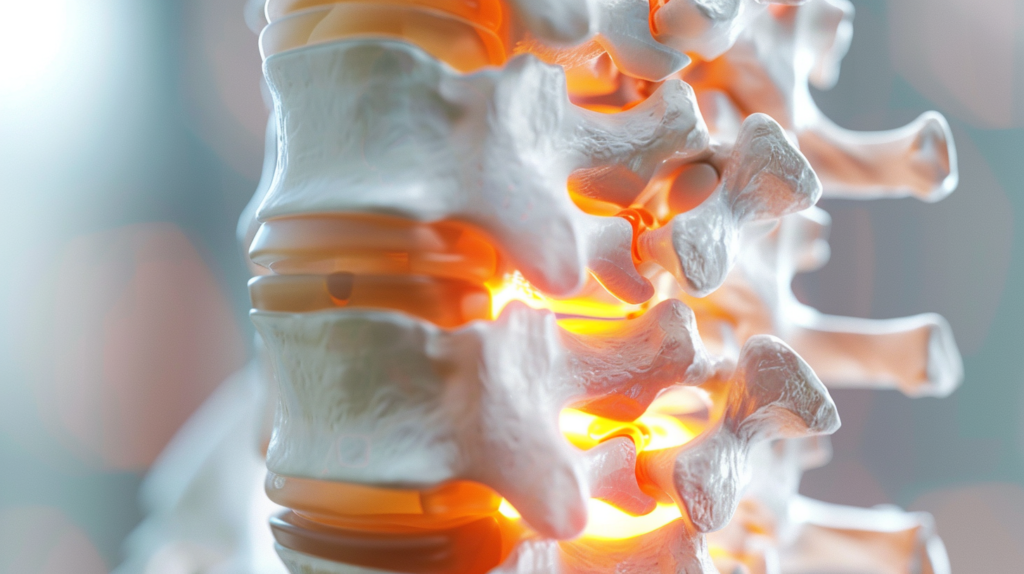

Остеохондроз поясничного отдела – это дегенеративное заболевание позвоночника, при котором происходят изменения в межпозвонковых дисках и окружающих тканях. Проще говоря, это процесс “изнашивания” нашего позвоночника, который чаще всего затрагивает именно поясничный отдел.

Почему именно поясница? Дело в том, что поясничный отдел несет на себе основную нагрузку при движении и поддержании веса тела. Представьте себе, что ваш позвоночник – это башня из кубиков. Нижние кубики (поясничный отдел) несут на себе вес всей конструкции, поэтому они и “изнашиваются” быстрее всего.

При остеохондрозе межпозвонковые диски, которые служат своеобразными амортизаторами между позвонками, теряют свою эластичность и высоту. Они становятся более плоскими и менее способными выполнять свою функцию. Это приводит к тому, что позвонки начинают сближаться, что может вызывать дискомфорт и боль.

Но на этом процесс не останавливается. Организм, пытаясь компенсировать эти изменения, начинает формировать костные разрастания – остеофиты. Эти костные шипы могут сдавливать нервные корешки, что приводит к еще большей боли и нарушению функций.

Чтобы лучше понять, что происходит при остеохондрозе, давайте совершим небольшое анатомическое путешествие по поясничному отделу позвоночника.

Поясничный отдел состоит из пяти крупных позвонков, обозначаемых от L1 до L5. Эти позвонки крупнее, чем в других отделах позвоночника, так как они несут на себе большую нагрузку. Между каждой парой позвонков расположен межпозвонковый диск.

Особое внимание стоит уделить нервным корешкам, которые выходят из спинного мозга через отверстия между позвонками. Именно сдавливание этих корешков при остеохондрозе часто является причиной острой боли и нарушения функций.

Из-за уменьшения высоты дисков и образования остеофитов нервные корешки могут оказаться зажатыми.